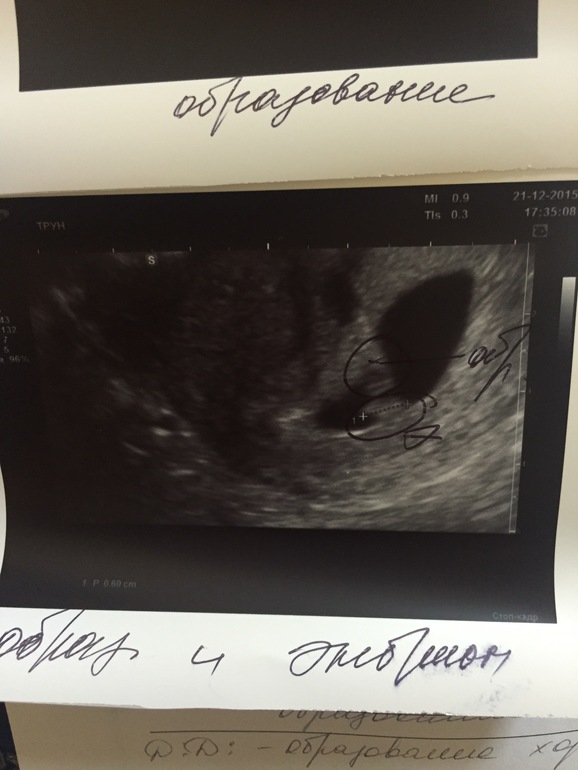

Вопросы про УЗИ, обследования и анализы: что, где, как, когда?Девочки,надеюсь на оргомныйпростор беби блога,т.к. В интернете почти ничего не нашла. Была вчера на узи, срок ставят 5-6 недель,эмбриончик ктр 5,8 мм с сердцебиением, желточный мешочек 3,3. Но, в плодном яйце есть еще одно образование размером 5х3 мм,Неправильной формы, без активного кровотока, бе четкой дифферинцированной структуры. Милые мой,кто с таким сталкивался,а еще важнее это опасно? Врачи разводят руки и не знают что сказать,вчера вообще смотрели в больнице на 2 аппаратах, т.к.первый врач только повторял "что-то не так,а что не так я не пойму".

Да это нереально😳😳да и срок такой что должно показывать ну хотя бы правильные размеры.. Врач говорит что нужно следить будет и удалять его на 20 неделе ,ну про это я поняла. Еще у нее вторая версия,что это "образование хориона" вот про это она мне вообще ничего не сказала что это и на сколько опасно...